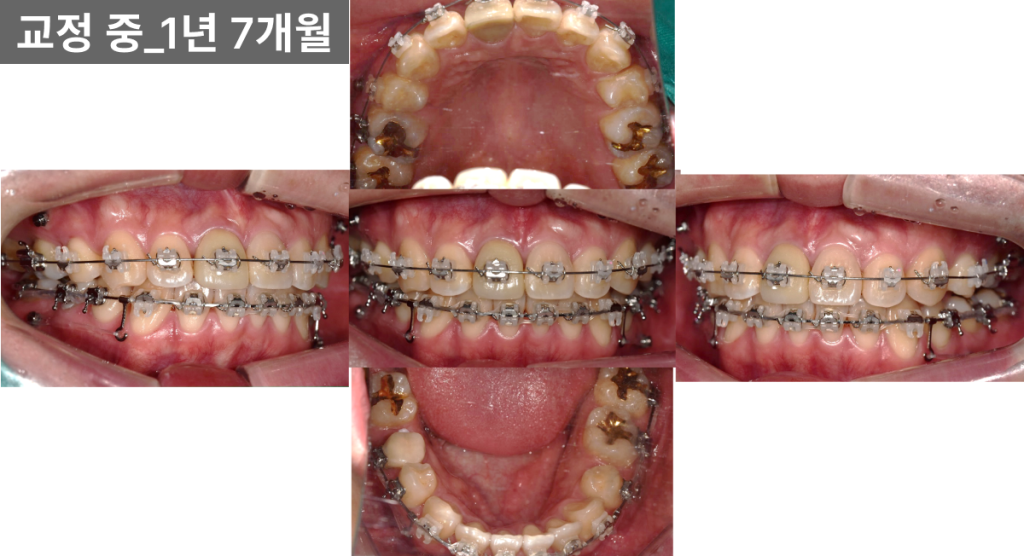

중간 단계 (약 1년 7개월)

윗니 발치 공간은 대부분 닫혔고

중심선도 비교적 안정적으로 맞아갔습니다.

다만 왼쪽 어금니 부위에서

교합이 들리는 양상이 보여

고무줄 사용과 철사 조절을 병행했습니다.